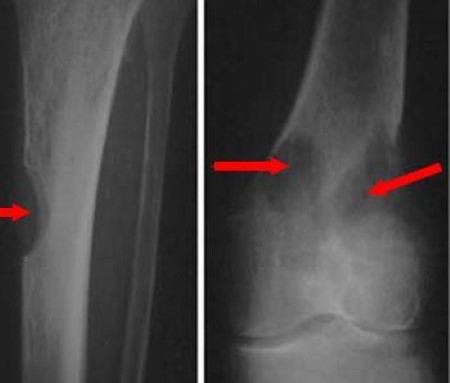

X-rays of multiple myeloma in leg

These X-rays show typical lesions caused by multiple myeloma. (Left) A lesion in the tibia (shinbone). (Right) Two lesions at the lower end of the femur (thighbone) near the knee.